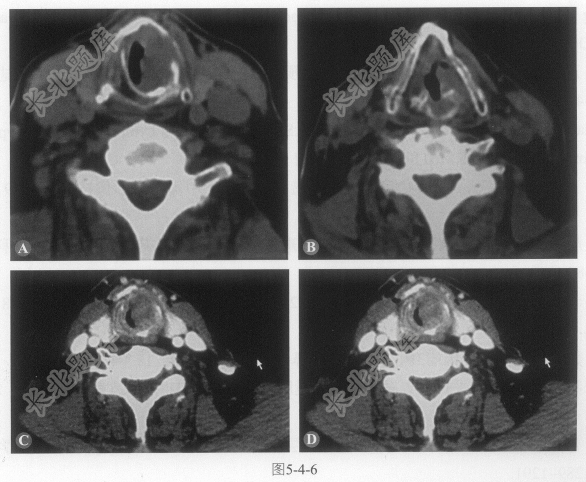

[材料题] 患者男性,68岁,左侧颈部无痛性肿物半年(图5-4-5)。

A、病变位于左侧颈部Ⅱ区

B、病变边界不清,内部可见低密度坏死及不规则壁的钙化

C、病变可见不均匀强化

D、病变与左侧颈动脉界线清晰

E、病变与左侧胸锁乳突肌分界不清